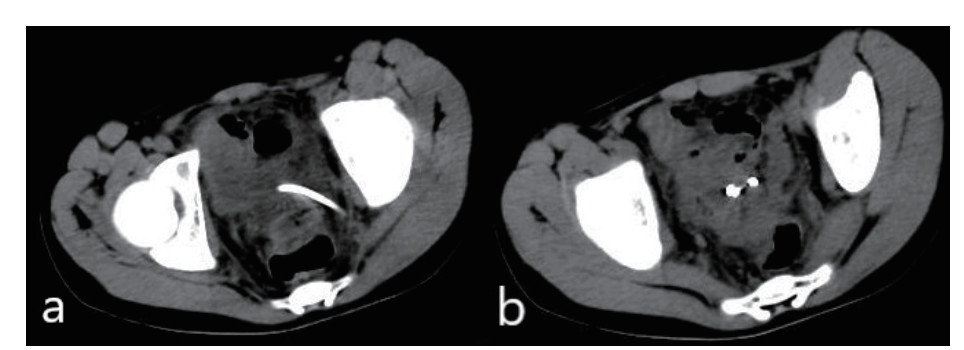

患者术后生命体征平稳,体温正常,引流管通畅,腹痛消失。术后3 d复查,血常规:白细胞6.73×109,中性粒细胞4.87×109;C-反应蛋白21 mg/L;降钙素原0.2 ng/mL;CT显示:盆腔可见引流管影,引流管周围未见明显积液(图 8)。脓液培养显示:大肠埃希菌。于术后4 d夹闭引流管,术后6 d拔除引流管,无明显并发症,顺利出院。术后6个月复查盆腔脓肿无复发。

| 图 8 术后腹腔CT显示:盆腔可见引流管影,引流管周围未见明显积液 |